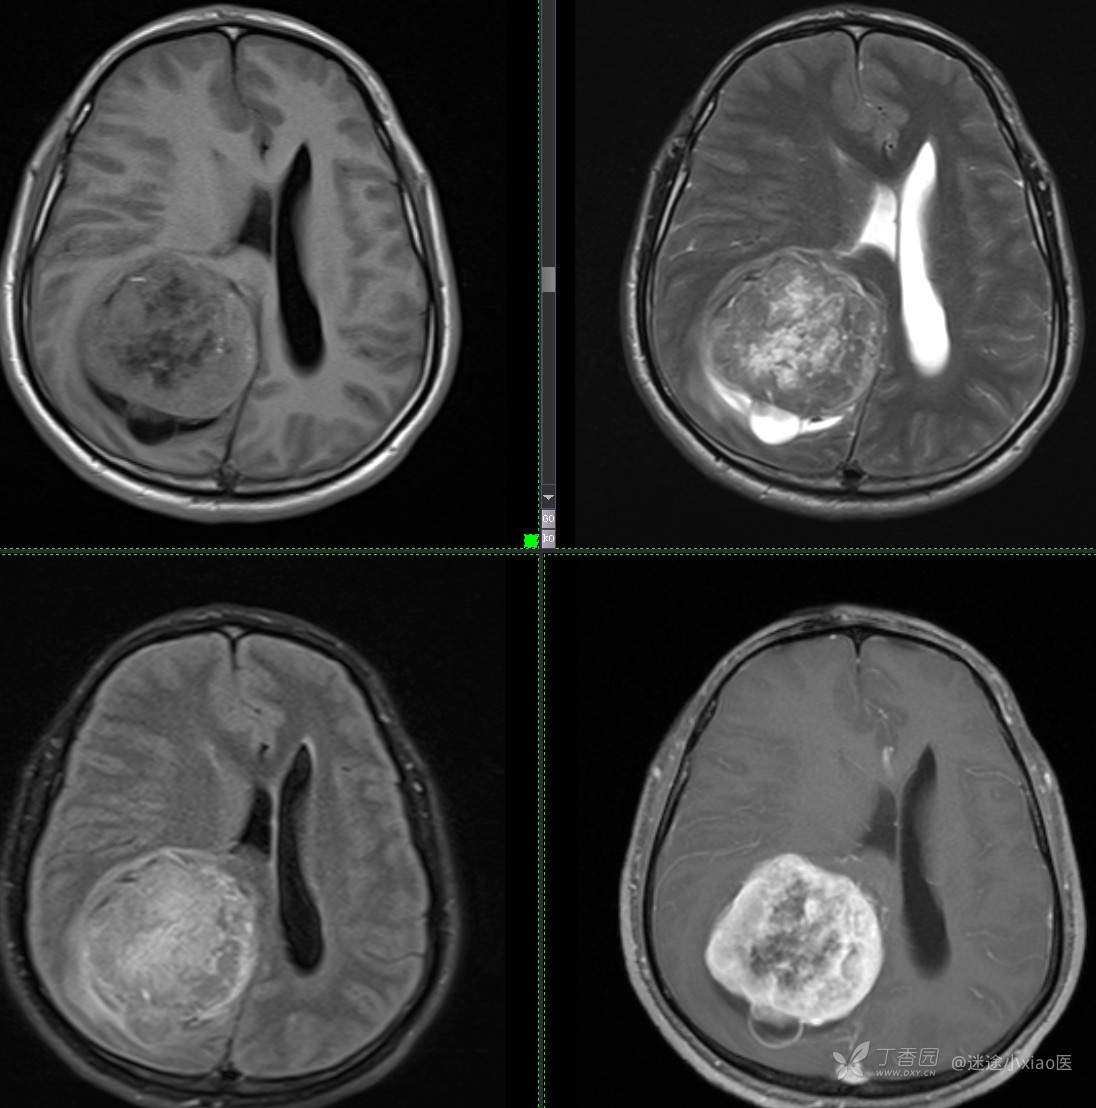

病例头颈组14:中年男性,显著强化病灶,如何考虑(结果公布)

如此典型病例,平扫即可诊断(结果公布)

患者年龄:43

患者性别:男

简要病史:头痛3月余,查体无殊